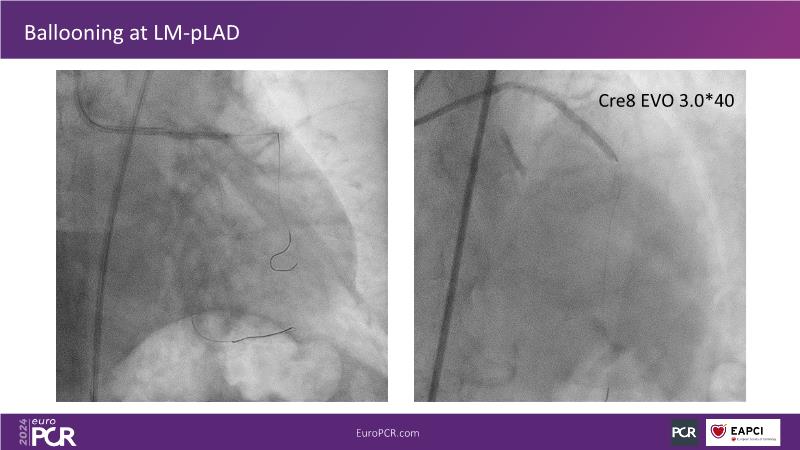

From innovation to reality: the impact of Cre8 EVO technology on complex PCI

This session is a good opportunity to delve into the contemporary technical and clinical complexities surrounding complex PCIs in challenging patient cases. Explore the necessary tools and treatment strategies to enhance peri-procedural and long-term clinical outcomes, and follow discussions on the unique technologies of Cre8 EVO in complex PCI scenarios.